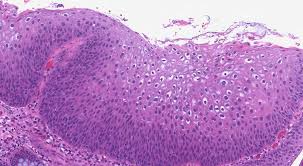

상피내암의 치료는 일반적으로 종양의 위치와 진행 단계에 따라 다르지만, 초기 단계에서 발견된 경우 치료의 목표가 매우 구체적입니다. 적절한 치료는 암세포의 완전 제거와 예방을 목표로 하며, 다음과 같은 방법이 있습니다:

첫 번째로, 수술적 치료는 상피내암 세포가 있는 부위를 절제하여 제거하는 방법입니다. 이 방법은 초기 단계에서 즉각적인 효과를 볼 수 있으며, 잘 진행될 경우 암이 더 이상 퍼지지 않도록 예방할 수 있습니다. 특히 자궁경부 상피내암의 경우, 전신 마취 하에 수술이 이루어지며, 종종 자궁이나 임파선까지 절제될 수 있습니다.

방사선 치료는 암세포를 파괴하는 데 도움을 주며, 수술 후 잔여 암세포 제거를 목표로 할 때 사용됩니다. 약물 치료는 항암제를 이용하여 암세포의 성장을 저해하는 방식이며, 면역 요법은 면역 체계를 강화하여 암을 스스로 퇴치하게끔 돕는 방법입니다. 이러한 치료들은 각각의 종류의 상피내암에 따라 다르게 적용될 수 있습니다.

상피내암의 치료에는 많은 전문가의 협력이 필요합니다. 종양학자, 외과의사, 방사선 전문의 등 다양한 전문의와의 상담을 통해 최선의 치료 방법을 찾아가는 것이 중요합니다. 조기 발견과 조기 치료는 환자의 생존율을 높이는 중요한 요소이며, 이러한 절차를 통해 상피내암 환자들은 치료에 긍정적인 결과를 기대할 수 있습니다.